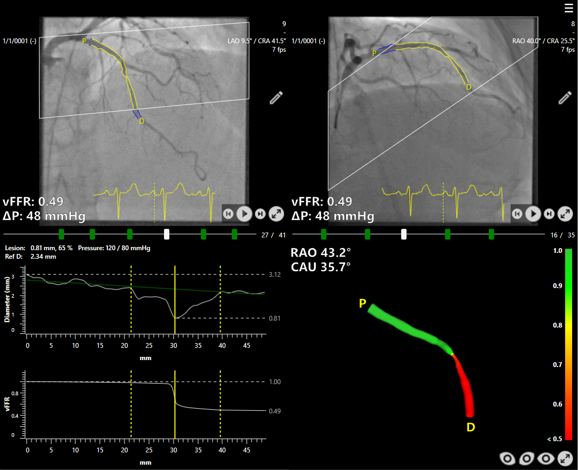

Today the results of the FAST III study, co-funded by Siemens Healthineers and Pie Medical Imaging, were presented at the Congress of the American College of Cardiology (ACC) and published in The New England Journal of Medicine (Angiography-Based Physiology to Guide Coronary Revascularization | New England Journal of Medicine). The results confirm the safety and efficacy of Caas vFFR – a software-based method developed by Pie Medical Imaging that calculates pressure drop and vessel fractional flow reserve from two angiographic images – as an alternative to conventional pressure wire-based physiology for guiding revascularization strategy in patients with intermediate coronary artery stenosis. This marks the end of the multicenter, randomized-controlled, open-label, non-inferiority study investigating the outcome of therapy for coronary artery disease after fractional flow reserve (FFR) has been determined using different methods. A total of 2,235 patients in 37 hospitals across seven European countries took part in the study, randomly selected for either the vFFR- or FFR-guided approach. FAST III marks the last important step in a ten-year evidence generation journey towards real-world outcome data.

Coronary stenoses are extremely common and clinically relevant as they sit at the center of coronary artery disease (CAD), the leading cause of death globally. FFR assesses how much coronary artery stenosis limits blood flow, with evidence showing that lesions causing less than a 20 percent flow reduction generally do not require treatment. Traditionally, FFR is measured by inserting a pressure wire into the coronary artery and inducing hyperemia with adenosine, a process that can cause the patients discomfort such as restlessness, chest pain, and shortness of breath. The FAST III study had evaluated whether percutaneous coronary intervention (PCI) guided by Caas vFFR can match the outcomes of the conventional invasive, pressure wire approach. This newer Caas vFFR technology offers a less invasive alternative by eliminating the need for both a pressure wire and hyperemic agents.

CAAS vFFR software by Pie Medical Imaging, as used in the FAST III study.